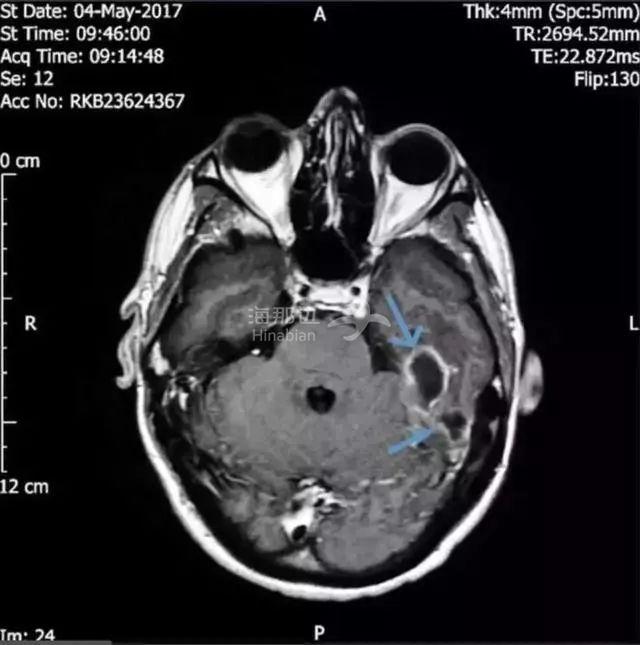

而这名男子的炎症由于推延了太久,已经向脑部延伸。医学团队的CT扫描显示:他的头骨下靠近左耳道的位置有两块充满脓液的肿块,再晚治疗情况就危险了。

图:男子的脑成像,箭头处为肿块

终于在脑成像的帮助下他们发现男子的耳道中有一个异物。经过鉴定,导致严重感染的东西是一小撮棉花。